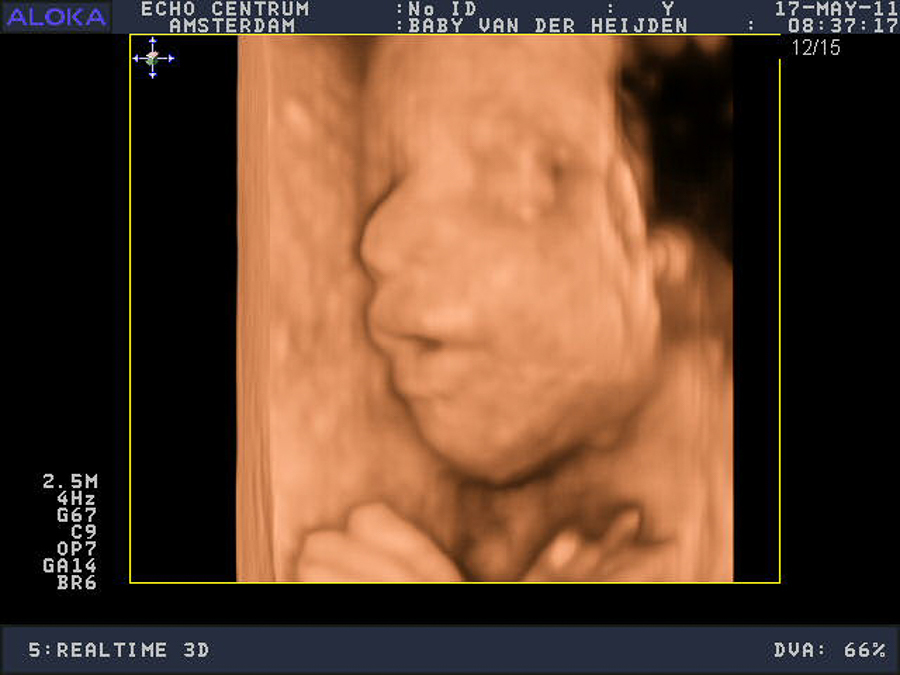

Echo’s die je zelf kan inplannen (pretecho’s)

Wil je een extra echo gewoon omdat je het leuk vindt, dus zonder medische noodzaak? Dan heet het een pretecho en betaal je de kosten hiervan zelf (€55,00). Bel of mail de assistent voor het inplannen van een pret-echo.

• Pret-echo, gewoon om de baby te bewonderen (tussen 8-39 weken)

Omdat een echo niet schadelijk is voor jou of de baby, kun je net zoveel echo’s laten maken als je zelf fijn vindt.